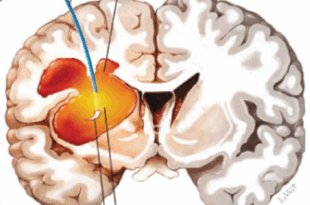

Read More »दिमाग की नस क्यों फटती है? ब्रेन हेमरेज के कारण और बचाव समझें आसान भाषा में

ब्रेन हेमरेज यानी दिमाग में खून का बहना एक गंभीर मेडिकल इमरजेंसी है। यह तब होता है जब दिमाग की कोई रक्त वाहिका (blood vessel) फट जाती है और खून आसपास के हिस्सों में फैलने लगता है। इससे दिमाग पर दबाव बढ़ता है और कई बार स्थिति जानलेवा भी हो सकती है। लेकिन अच्छी बात यह है कि इसके प्रमुख …